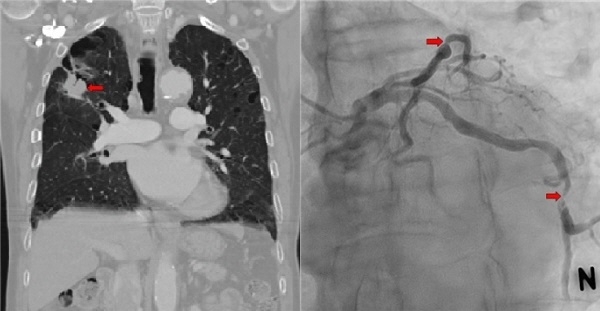

왼쪽/ 우상엽 폐암의 CT소견 (화살표), 오른쪽/ 관상 동맥 협착 (화살표)